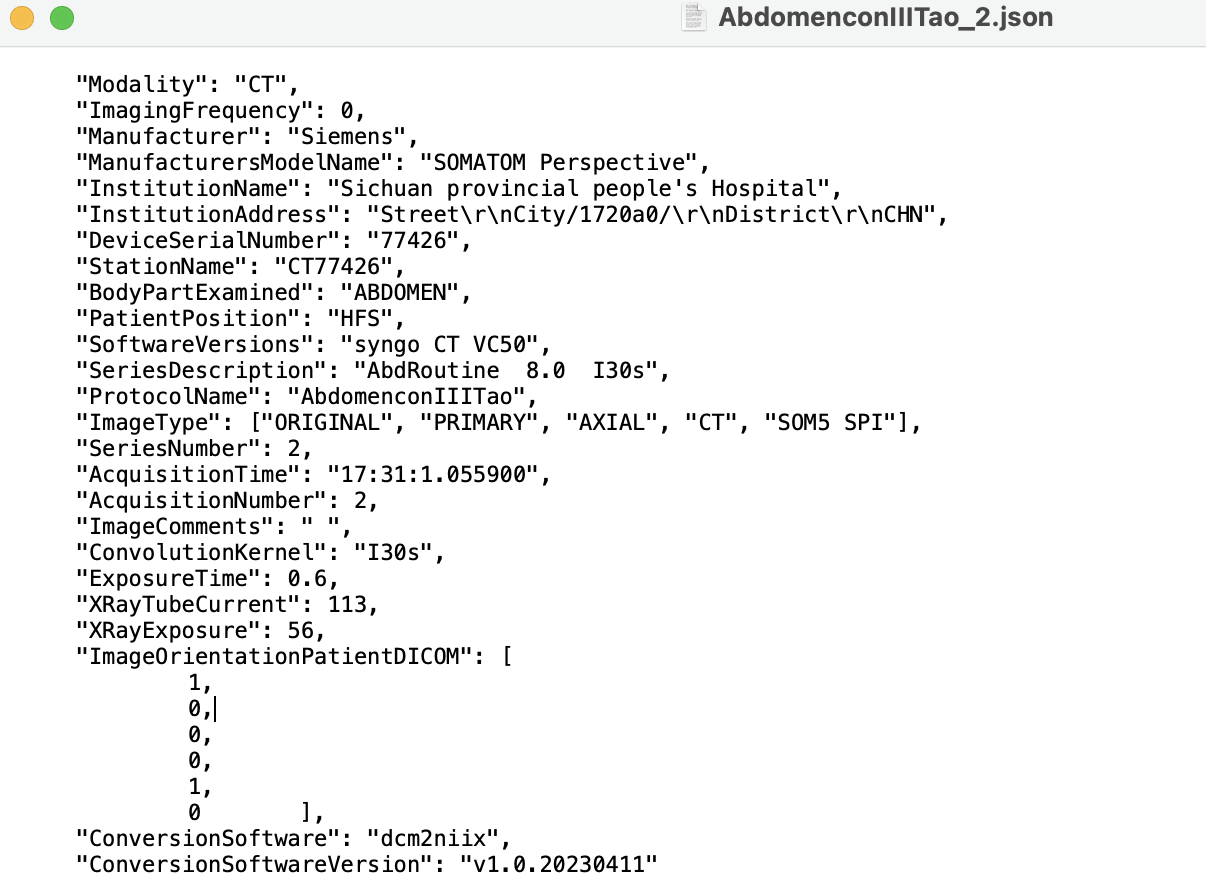

- -b: BIDS sidecar:(“-b y”或“-b n”, 默认为 y)如果选择“yes”,则软件将生成与NIfTI图像同名的一种Brain Imaging Data Structure文件。该文件采用JSON文本格式,提供了有关扫描的附加信息,这些信息无法保存在NIfTI头文件中